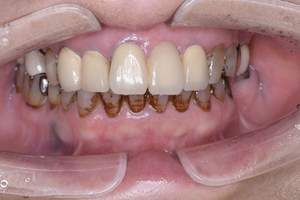

治療前 1

治療後 1

治療前 2

治療後 2

治療前 3

治療後 3

| 年齢 | 58歳・女性 |

|---|---|

| 主訴 | 前歯の着色除去希望 |

| 治療内容 | エアフロー |

| 費用 | 合計:5,500円 (2024年8月現在) |

| 治療期間 | 60分 |

| リスク・副作用 | 呼吸器疾患のある方や放射線治療を行っている方、ナトリウム摂取制限を必要とする方や妊娠中の方は処置を受けられないことがあります。 施術を受ける際、舌や歯肉に当たった粒子でチクチクとした痛みを感じることがあります。 |

| 治療方針 | 歯周病と虫歯の治療を担当医と相談し進めていく予定です。 |

| 担当者所見 | 約4年ぶりの来院でした。他の歯医者に行っても満足いくクリーニングをしてもらえず悩んでいる様子でした。問診時には手で口元を隠すようにお話されていましたが、エアフロー後は笑顔でお話するようになっていました。 |